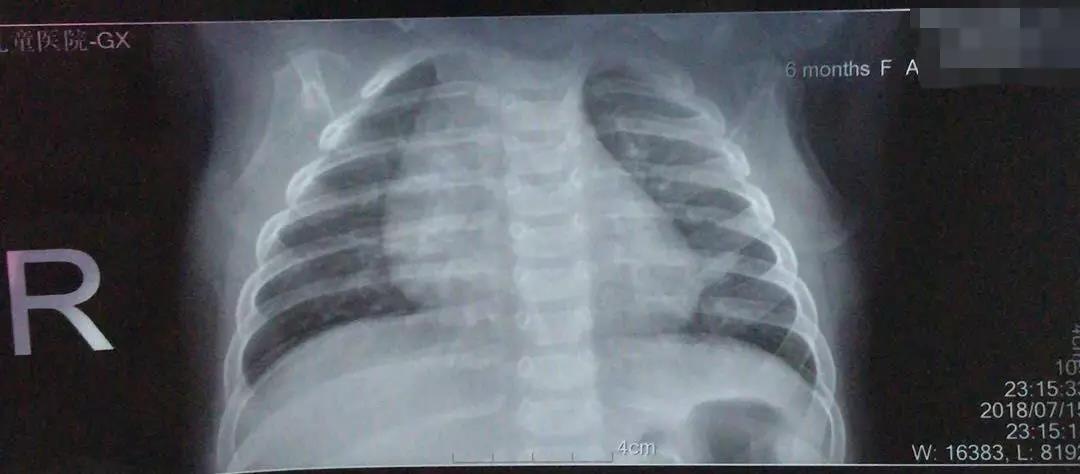

没想到两天后因为受凉咳嗽又加重了,转眼间过去了一个多星期,妈妈真的着急了,再次抱着孩子去了医院,这次医生听诊肺里有啰音,要求家长带孩子拍一个胸片,报告显示肺炎,开了抗生素静脉输液了。

——【胸片】

妈妈还是不放心6个月大的孩子,已经是第二次肺炎了,很紧张,也很害怕,该怎么办呢?找到我的时候,我看孩子的精神很好,笑嘻嘻的挺高兴,面色也正常,呼吸有点粗,不快,有痰声,用听诊器听听确实有啰音,看了孩子的化验结果和胸片我仍坚持不需要输液治疗。

3岁之内的宝宝出现的咳嗽或喘息可能只是一种良性的自限性疾病,随着孩子的生长发育,可能会逐渐缓解,这个年龄段的喘息并不是将来全都会进展成哮喘。这时候拍个胸片显示有絮状的片状阴影,也不一定就是肺炎,也许只是一种炎症渗出,此炎可不是细菌性炎症哦 。总而言之,一定要弄清病因,需要抗细菌时要刻不容缓,如果是过敏反应要避免过敏原刺激。